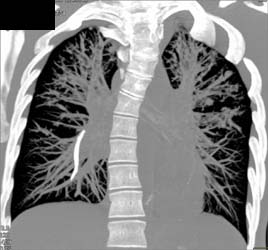

Lung Cancer